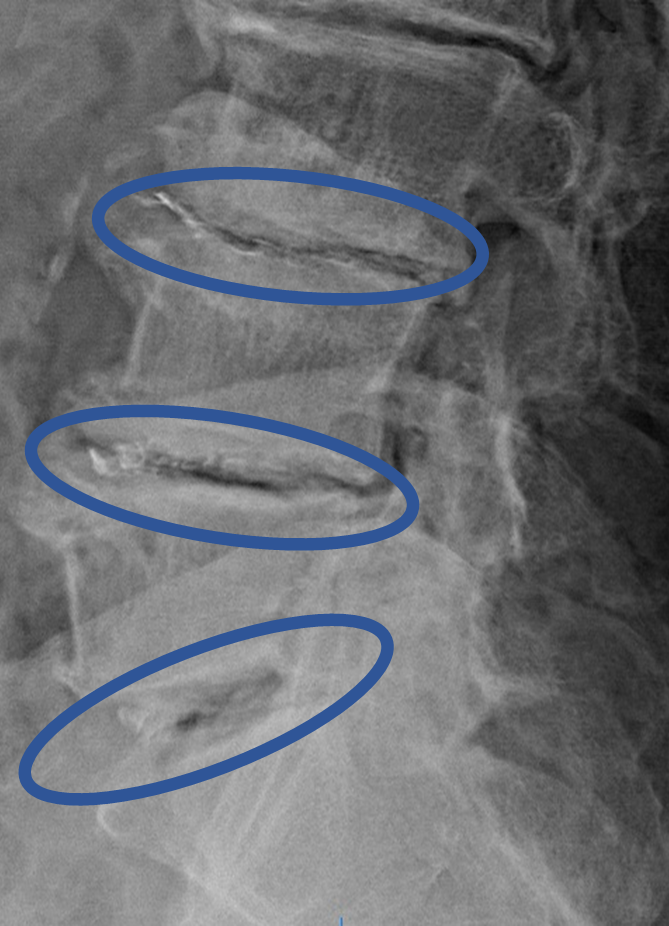

画像及び所見について

L1/2: 椎間板変性、減高

L2/3: 椎間板変性、減高

L3/4: 椎間板変性、減高、繊維輪断裂

L4/5: 椎間板変性、膨隆、右椎間孔狭窄

L5/S: 椎間板変性、膨隆

以上の事が画像上認められます。

L3/4、4/5、5/S に

椎間板変性、減高、膨隆、繊維輪断裂、椎間孔狭窄 を認め、主症状の原因の可能性が高い。

DiscoGelを入れた後の画像になります。